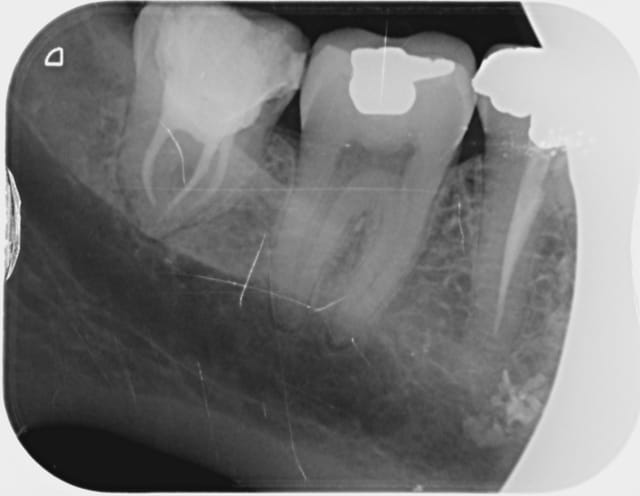

Pano plombee l7p4ix - Eugenol

01 ukhwbq - Eugenol

On lui avait dit de pas se planquer dans la haie pendant la chasse ^^

Pis c'est du gros plomb, je dirais du 2.

ha non c'est pas des plomb de chasse ca.

C'est quoi de la peinture, de l'allu découpé?

C'est sur le patient et pas a l'interieur ni sur le capteur de la pano, donc je dirais une sorte de peinture cuttané ou allu.

Un truc pour faire des mouches?

Putain de piercing.

je crois pas on voit le pins sur la plus part des piercing, plus le dentiste ne s'est pas aperçus qu'il y avait quelque chose de radio dense (a moins qu'il est fait une irradiation pour le fun).

Donc peinture, poudre ou l'on ne savait pas que c'était radio dense.

Probablement patient vue en urgence pour un pulpite sur 37 ou 38 et qui allait a une féte ou un carnaval.